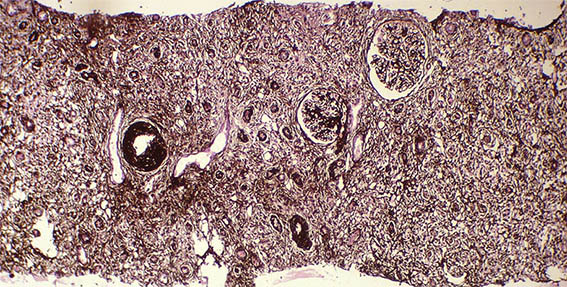

Figura 1. H&E, X100. Note el prominente compromiso tubulointersticial.